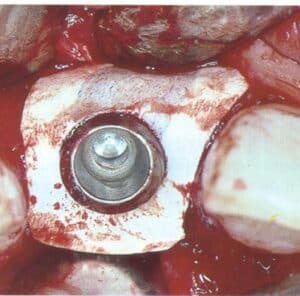

Tissue level implants (some of them hollow cylinder), back then the “ITI system”, were placed in fresh extraction sockets, augmented with GBR and let to heal transmucosally and later be restored with solid abutments. Today I could have considered this impossible, if it wasn’t for a well documented study. The year was 1996, in Bern by Brägger, Hämmerle and Lang. Twenty seven years later, all three were part of the ITI Consensus in Lisbon which accepted A1 immediacy as treatment of choice.

Likewise, the attempt to bring immediacy into the mainstream around 2004 proved to be a bridge too far. The commercial vehicle to materialise the promises of immediacy was soon launched and it was no other than implants designed for placement in extraction sockets aiming to receive immediate provisionals and promising to preserve tissue. Nobel Perfect and Nobel Direct, were two implants launched and marketed as the “immediacy” implants. They were one-piece implants with certain features that were expected to optimise outcomes of placement in fresh extraction sockets. Among these was the provision for a cement retained crown, the lack of an implant-abutment “gap” and also the coronal extension of rough surface, which was envisioned to enhance the attachment of the soft tissue. For this purpose and also to support interproximal papilla, Nobel Perfect had scalloped margins of the rough surface. The spatial positioning of an immediate implant at that time was also not perceived as today; there was a misguided view that filling the socket with titanium was the element which lead to bone preservation. This might be the principle behind another immediacy implant, around that time from Straumann, the TE implant which was a tissue level implant with characteristically wider coronal part.